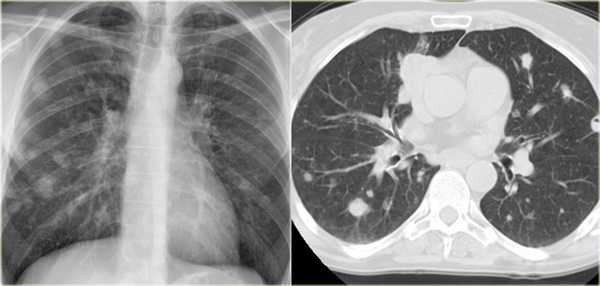

Дифференциальный диагноз множественных очагов в легких очень длинный. Наиболее частые представлены в таблицы. Очень часто трудно отдифференцировать множественные очаги от мультифокальной консолидации.

Метастазы

Метастазы являются частой причиной множественных очагов легких. Обычно очаги различные по размеру, с четкими контурами и чаще локализуются в нижних долях и субплевральной области легких. На КТВР множественные очаги обычно визуализируются, как очаги, локализующиеся произвольно не так, как при многих заболеваниях перилимфатически или центролобулярно. На снимках визуализируется почечно-клеточная карцинома, прорастающая в нижнюю полую вену и последующим распространением в легкие.

![ra73]()

Ниже представлен другой пациент с метастазированием легкого. Первичная опухоль в языке.

![ra74]()